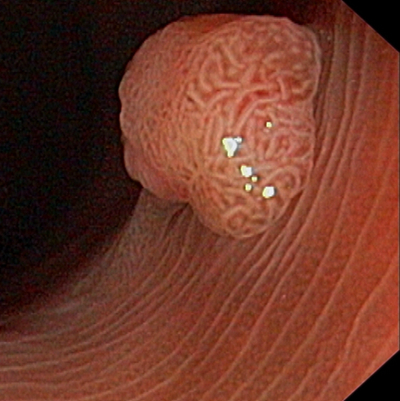

肛門癌圖片

肛癌早期症狀